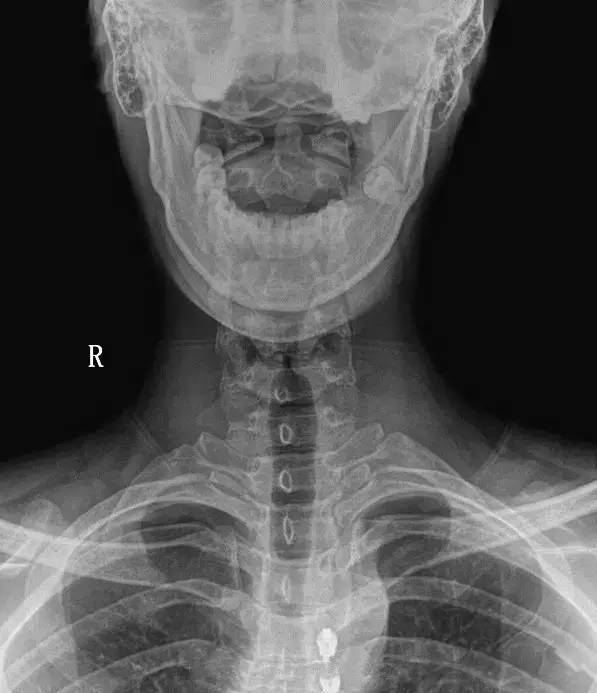

一招教你如何读懂"颈椎正位片"

图片尺寸554x753

颈椎正位

图片尺寸1080x810